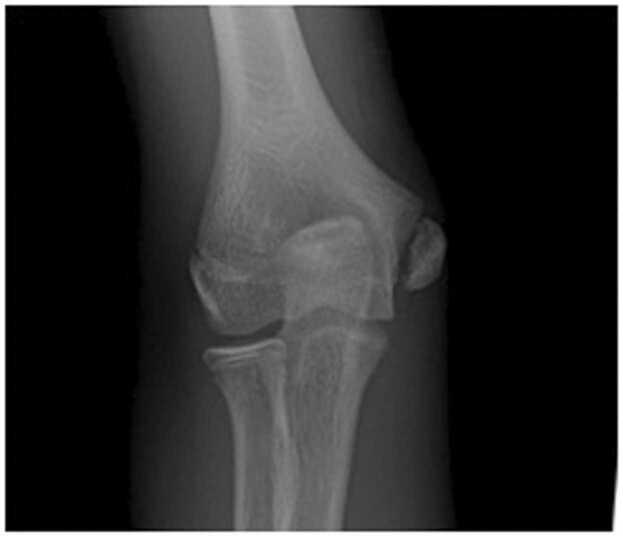

儿童和青少年的应力性骨折与过度使用损伤

Stress fractures and overuse injuries in children and adolescents.

There is an intricate connection between physical activity, bone health, and the susceptibility to stress fractures and overuse injuries. Physical activity has a positive impact on bone strength while a sedentary lifestyle can lead to a heightened risk for injury. The rise of early sports specialization has led to a substantial increase in overuse injuries, particularly in individual sports.Bone Stress Injuries (BSI) represent a category of overuse injuries closely linked to single sport specialization. BSI involves a spectrum of altered bone mechanics, ranging from edema of periosteum, endosteum, and bone; potentially leading to partial or full cortical breaks. This condition is prevalent in high-level athletes and encompasses stress reactions and fractures, resulting from an imbalance between injury creation and repair. Up to 20% of adolescents are affected, with the tibia being the most common location, predominantly occurring in athletes aged 15 to 25. A holistic approach integrating both physical and nutritional aspects is warranted to ensure sustained musculoskeletal health across diverse pediatric and adolescent groups and athletic endeavors.

身体活动、骨骼健康以及应力性骨折和过度使用损伤易感性之间存在复杂的联系。身体活动对骨骼强度有积极影响,而久坐不动的生活方式会增加受伤风险。早期运动专项化的兴起导致过度使用损伤大幅增加,尤其是在个人运动项目中。骨应力损伤(BSI)是一类与单一运动专项化密切相关的过度使用损伤。BSI涉及一系列改变的骨力学,范围从骨膜、骨髓膜和骨骼的水肿;可能导致部分或完全皮质断裂。这种情况在高水平运动员中很普遍,包括应力反应和骨折,是由损伤产生和修复之间的不平衡导致的。高达20%的青少年受到影响,胫骨是最常见的部位,主要发生在15至25岁的运动员中。需要一种综合身体和营养方面的整体方法,以确保不同儿科和青少年群体以及体育活动中的肌肉骨骼健康持续良好。

Retrospective Review of Radiographic Imaging of Tibial Bony Stress Injuries in Adolescent Athletes With Positive MRI Findings: A Comparative Study.回顾性分析 MRI 阳性的青少年运动员胫骨骨应力性损伤的影像学表现:一项对比研究。

Sports Health. 2023 Mar-Apr;15(2):244-249. doi: 10.1177/19417381221109537. Epub 2022 Aug 2.